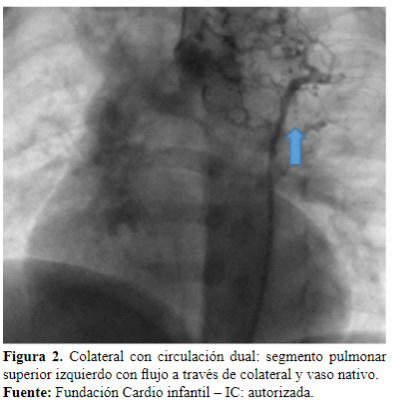

Realizado el diagnóstico, continúa la fase intervencionista; en cateterismo se realiza una embolización de colaterales, se canaliza la colateral superior izquierda que nutre el mediastino superior (Figura 2), la cual se emboliza con coil de Gianturco 38-4-3, resultando en un procedimiento exitoso y sin complicaciones, con evidencia de disminución del flujo sanguíneo de este segmento pulmonar (Figura 3).